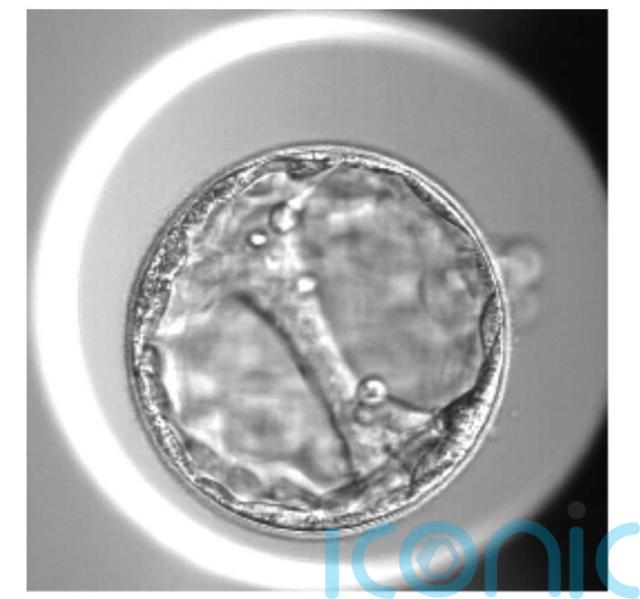

A woman who was conceived by IVF in the 1990s has just welcomed her own IVF baby into the world after struggling to conceive for just under five years, battling baby loss, chemical pregnancies and abnormal smear test results.

Lauren Gadsby, 33, and her husband, Jon, welcomed their healthy baby, Hollie, on December 8 2025, after an IVF journey that saw them lose three pregnancies.

Upon hearing the news, they decided to try IVF, supported by supplements including Impryl® from Fertility Family, which is said to help optimise fertility and support a healthy pregnancy. Since Lauren herself was the product of IVF, they felt confident in the process and were willing to do whatever they needed to have a baby of their own.

In April 2024, Lauren had her egg collection procedure, and they were fortunate to get “quite a few embryos”.